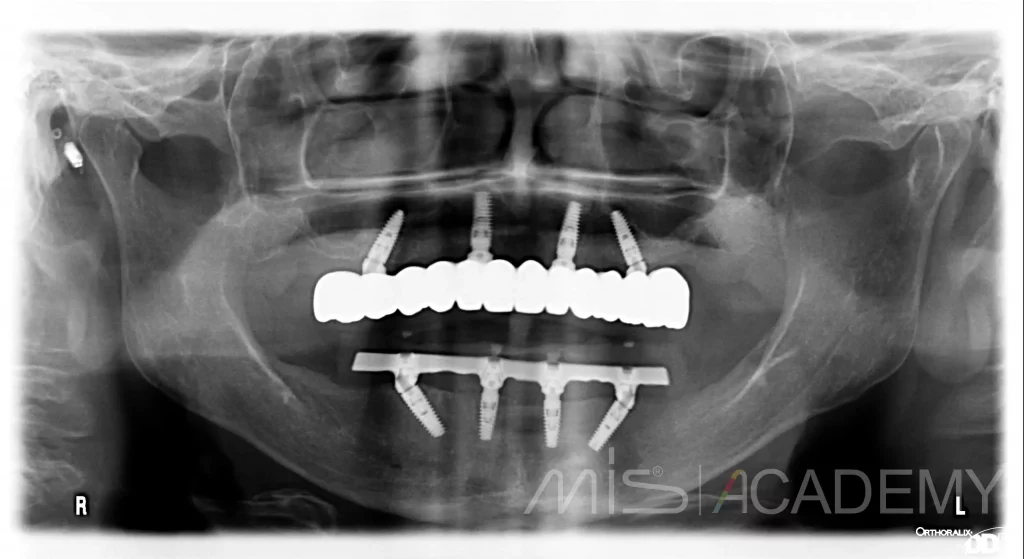

Тотальное восстановление зубного ряда

1. Установили по 4 имплантата на верхней и нижней челюсти и провели немедленную нагрузку металлопластмассовыми конструкциями.

2. После интеграции изготовили постоянные конструкции на верхней челюсти FP1 из диоксида циркония на титановой балке, на нижней челюсти FP3 из металлокомпозита.

3. Работа проводилась частично в цифровом протоколе, однако модель верифицировали при помощи гипсовых трансферчеков для избегания напряжения в конструкции.